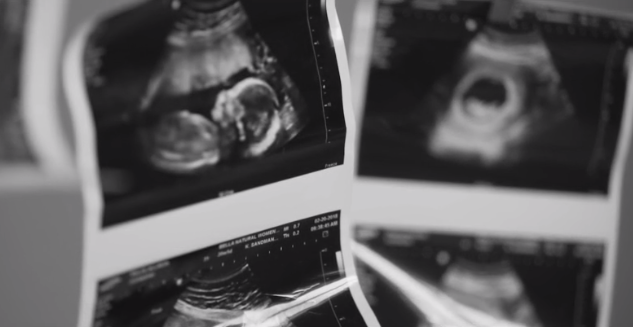

She quickly got an appointment with Bella Health and Wellness where they performed an ultrasound.

Her baby was still alive.

“I could hear the baby’s beautiful heartbeat – strong and steady,” the mom said.

“Once I heard that, there was no going back,” she said. “I was going to fight for that baby.”